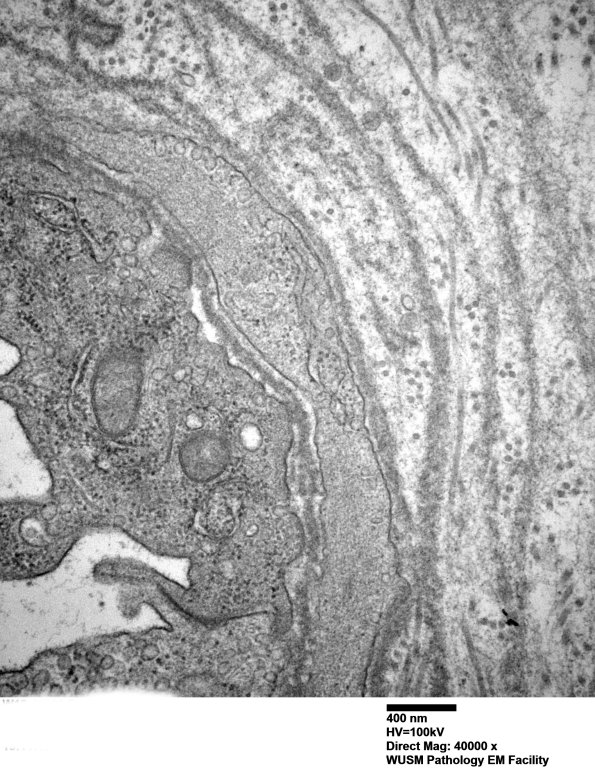

Washington University Experience | VASCULAR | Hypoxia-Ischemia, fetal-neonatal | White Matter | 13C4 (Case 13) EM026 - Copy

13C4 (Case 13) EM026 - Copy